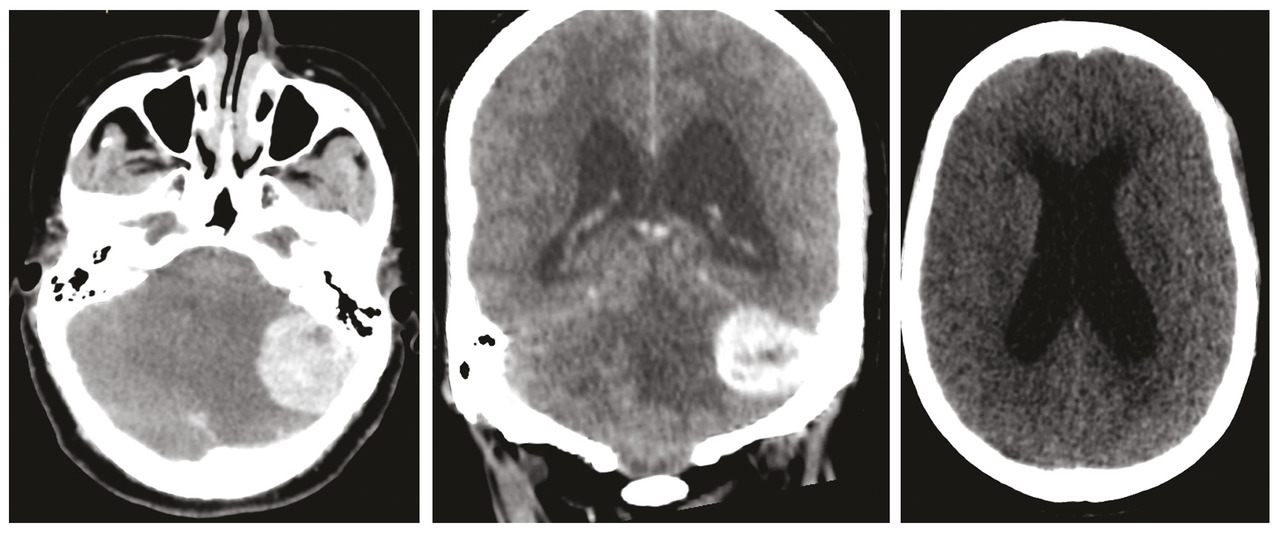

Une femme de 32 ans, sans antécédents pathologiques, consulte pour baisse brutale de l’acuité visuelle. L’examen ophtalmologique trouve un œdème papillaire bilatéral, le reste de l’examen neurologique est sans particularités. Face à cette symptomatologie, un scanner cérébral est réalisé en urgence. Il montre un processus cérébelleux gauche responsable d’un effet de masse sur le quatrième ventricule avec une hydrocéphalie d’amont et des signes de résorption transépendymaire (fig. 1 ). Par la suite, la patiente a bénéficié d’une dérivation ventriculo-péritonéale. Une imagerie par résonance magnétique (IRM) cérébrale a été réalisée pour une meilleure analyse. Elle a permis d’objectiver un processus intra-axial cérébelleux gauche bien limité à double composante kystique et charnue majoritaire en hyposignal T1-hypersignal T2 sans restriction sur la diffusion et se rehaussant de façon intense après injection de chélates de gadolinium (fig. 2 ). La patiente a été opérée (résection en monobloc de la tumeur) (fig. 3 ). Le diagnostic d’hémangioblastome a été confirmé à l’examen anatomopathologique. La patiente s’est améliorée par la suite sur le plan neurologique mais elle a conservé une cécité définitive.

À l’imagerie, le nodule mural est isodense au parenchyme cérébral avec rehaussement intense après contraste, les parois kystiques ne se rehaussent généralement pas et les calcifications ne sont pas fréquentes. On peut observer également à l’IRM des vides de signal sur la séquence T2 qui correspondent aux vaisseaux, et à l’IRM de perfusion les valeurs du rCBV (regional cerebral blood volume ou volume sanguin cérébral régional) sont élevées.